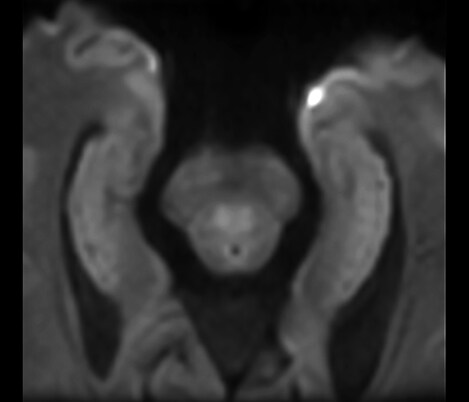

De la colaboración El Dr. Tetsuya Yoneda, Universidad de Kumamoto, Japón, habla sobre su colaboración con Philips en una técnica llamada SWIp desarrollada para la imagenología ponderada por susceptibilidad.

...a la práctica clínica El Dr. Chip Truwit, Centro Médico del Condado de Hennepin, Minneapolis, EE. UU. explica cómo SWIp se convirtió en una parte integral de todas las exploraciones de traumatismo por resonancia magnética.